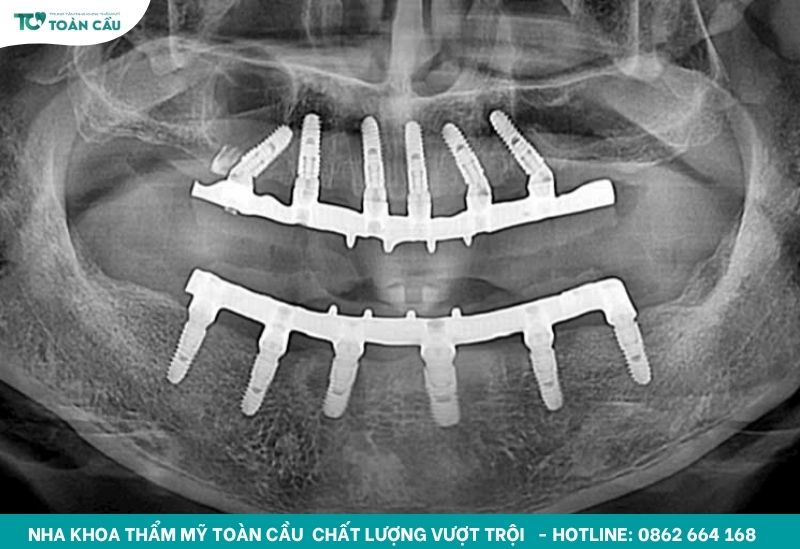

Kết luận cuối cùng là không phải mọi trường hợp lung lay đều phải tháo bỏ. Bạn cần được thăm khám kỹ lưỡng bằng phim X-quang để bác sĩ xác định chính xác giải pháp điều trị.

Công nghệ hiện đại được áp dụng xuyên suốt quy trình, bao gồm Scan 3D, thiết kế CAD/CAM và kỹ thuật Guided Surgery. Nhờ đó, implant được đặt chính xác vào vị trí, đảm bảo sự tích hợp xương tối ưu và giảm thiểu rủi ro lung lay sau này.